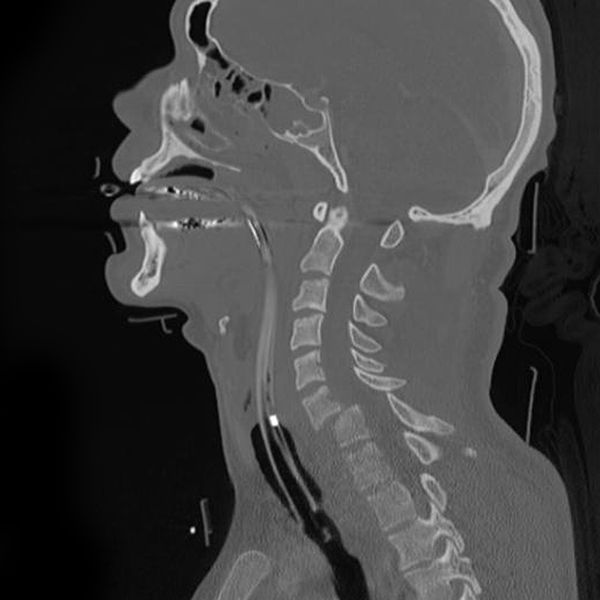

ब्रोकन नेक को डायग्नोस करने के लिए डॉक्टर आपसे पूछेगा कि आपको चोट कैसे लगी। इसके अलावा गर्दन और उसके आस-पास के हिस्सों में होने वाले दर्द और अन्य लक्षणों के बारे में पूछेगा। वह मांसपेशियों में होने वाली किसी तरह की परेशानी, आपकी सजगता और टच सेंस की भी जांच करता है। इसके अलावा आपको कुछ टेस्ट के लिए भी कहा जा सकता हैः

एक्स रे- गर्दन की हड्डी के टूटने या गर्दन में किसी अन्य तरह की समस्या की जांच के लिए एक्स-रे किया जाता है।

CT स्कैन या MRI- स्पाइनल कॉर्ड में होने वाली क्षति की जांच के लिए CT स्कैन या MRI किया जाता है। पिक्चर में आपका स्पाइल कॉर्ड बिल्कुल स्पष्ट दिखे इसके लिए आपको कॉन्ट्रास्ट लिक्विड दिया जा सकता है। यदि आपको कॉन्ट्रास्ट लिक्विड से एलर्जी है तो पहले ही डॉक्टर को इस बारे में बता दें।